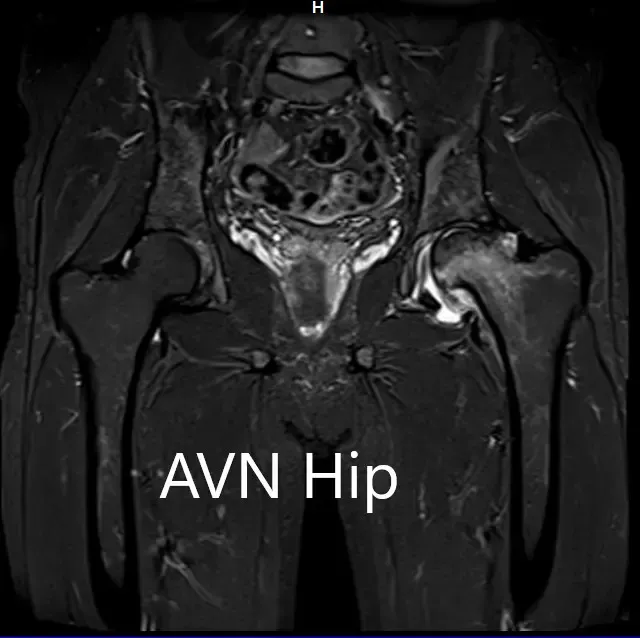

An MRI was obtained for diagnostic confirmation and staging of the disease. The left femoral head was collapsed with irregular contour and showed areas of altered signal intensity with a line of demarcation. Hypointense areas both on T1WI & T2WI seen in head suggestive of sclerosis. Surrounding marrow edema was seen

The left hip had advanced avascular necrosis with a collapse. The right hip was uninvolved presently. He was educated about the worsening collapse of the hip joint leading to his symptoms. Although the patient was young, he was advised a total hip replacement surgery in view of the collapse of the head of the femur with arthritis.